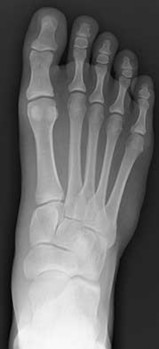

Figures 1a through 1c

Tarsal coalitions occur when primitive mesenchymal cells fail to differentiate and form the

normal articular separations between the tarsal bones of the hindfoot. Overall incidence is difficult to determine because many affected people are minimally symptomatic or asymptomatic. Symptomatic tarsal coalitions typically present in adolescents as a painful flatfoot; however, there are a number of possible presentations, and occasionally symptoms do not appear until adulthood. Most tarsal coalitions are between the calcaneus and the navicular (CN) and the talus and the calcaneus (TC). Although most TC coalitions are across the middle facet, posterior facet coalitions do occur. Plain radiographic evaluation of suspected tarsal coalition is the mainstay for diagnosis. However, coalitions can be bony or fibrous, and making the diagnosis can be difficult. The addition of CT images to distinguish bony definition and MR images to decipher soft tissue can aid in diagnostics. Bony coalitions appear as definite bony bridging between the bones, while fibrous coalitions are suspected when distortion of the bony anatomy is seen. Bony coalitions are best seen on the oblique view (CN) and Harris axial view (TC). There are a number of secondary signs such as the anteater (AE) sign (elongation of the anterior process of the calcaneus as it extends to the navicular as seen on the lateral view [CN]). talar beaking (traction spur of the talar neck thought to result from abnormal stresses as seen on the lateral view [both CN and TN]), and the “C” sign (a continuous cortical contour from the medial talus to the sustentaculum tali [ST]) as seen on the lateral view (TC). A number of newer signs are not as well known, such as a broad mediolateral dimension of the navicular on the anteroposterior (AP) view (the

navicular is wider than the talar head [CN]), nonvisualization of the middle facet on the lateral view (TC), the brick sign (a normal ST is flat, but a distorted ST is enlarged and curved [CN]), and a tapered lateral navicular bone as seen on the AP view (the medial navicular [CN] is much thicker than the lateral navicular).

Figure 1a shows talar beaking (TB), an AE, and an open middle facet (MF). Figure 1b shows a wide navicular (WN), and Figure 1c shows an abnormal articulation between the calcaneus and the navicular, all consistent with a CN coalition.